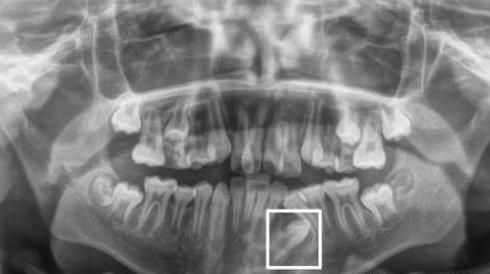

比如,拍片顯示牙槽骨內(nei) 有恒牙,隻不過完全埋伏在下麵了。這種如埋伏阻生造成的,可以谘詢正畸醫生是否能通過正畸或者是手術把牙齒牽引到合理的位置;

埋伏牙